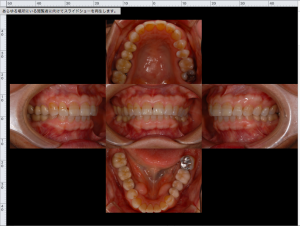

さてポプラ歯科医院では来院された患者さんのお口の中の写真を撮影し、記録をしております。(全員ではありませんが、基本は撮影しています。)

普段鏡越しでご自身のお口の中をみたことがあるかもしれませんが、奥歯など見えにくい部分もはっきりみることができます。

このお口の中の写真を記録することで過去の記録と照らし合わせ、歯周病の進行度を確認することもでき我々の診断にも大きく関わっております。

より精密にお口の中の検診をポプラ歯科医院で受診しませんか?